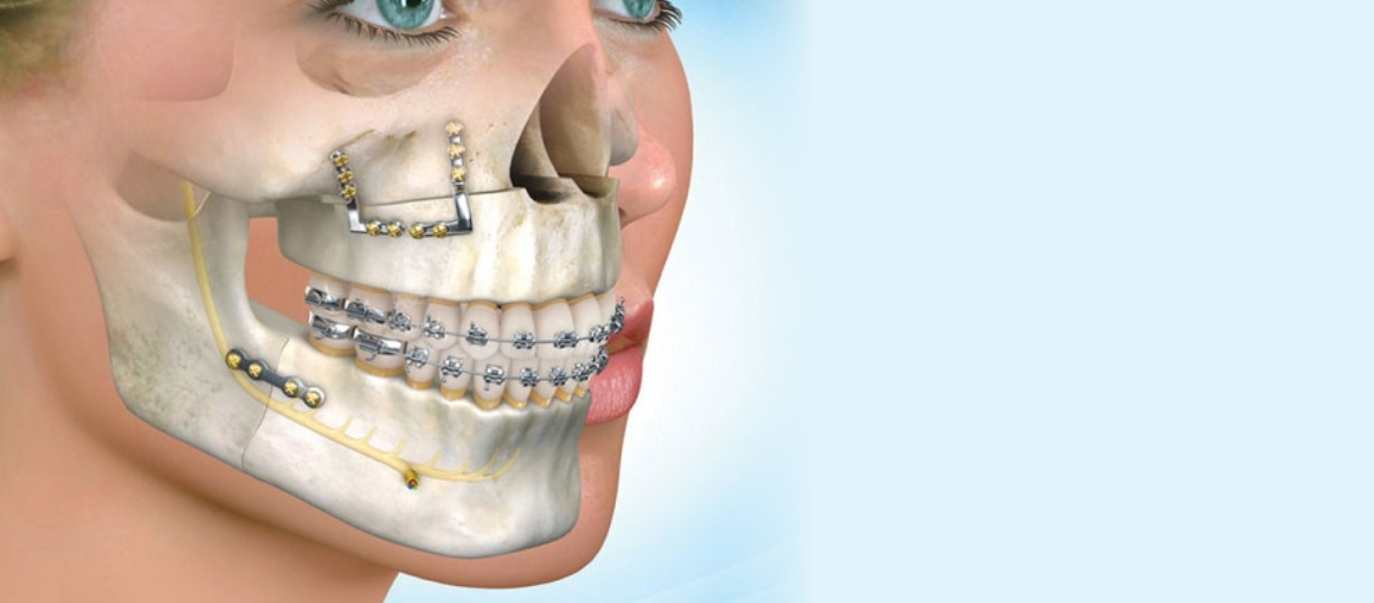

Cerrahi Tedaviler

Ağız, Diş ve Çene Cerrahisinde yapılan tedaviler daha çok gömük yirmi yaş çekimi olarak düşünülmektedir.

Ortodonti

Diş çapraşıklıkları çocukluk döneminde süt dişlerin yerini asıl dişlerin alması ile başlayan bir süreçtir.